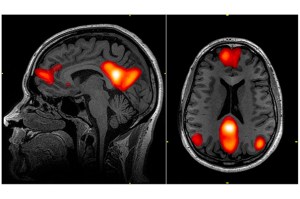

Whole brain imaging

New research led by Professor Jeff Lichtman opens a path to deeper insight on brain action behind certain behaviors.